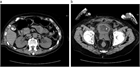

1. 尿閉とは膀胱内の尿を全く排出できないか、排出するのがきわめて困難な状態で、多量の残尿が常時ある状態である。

1. 男女共に尿閉の原因は様々であり、時に重大な背景疾患が隠れていることがある。